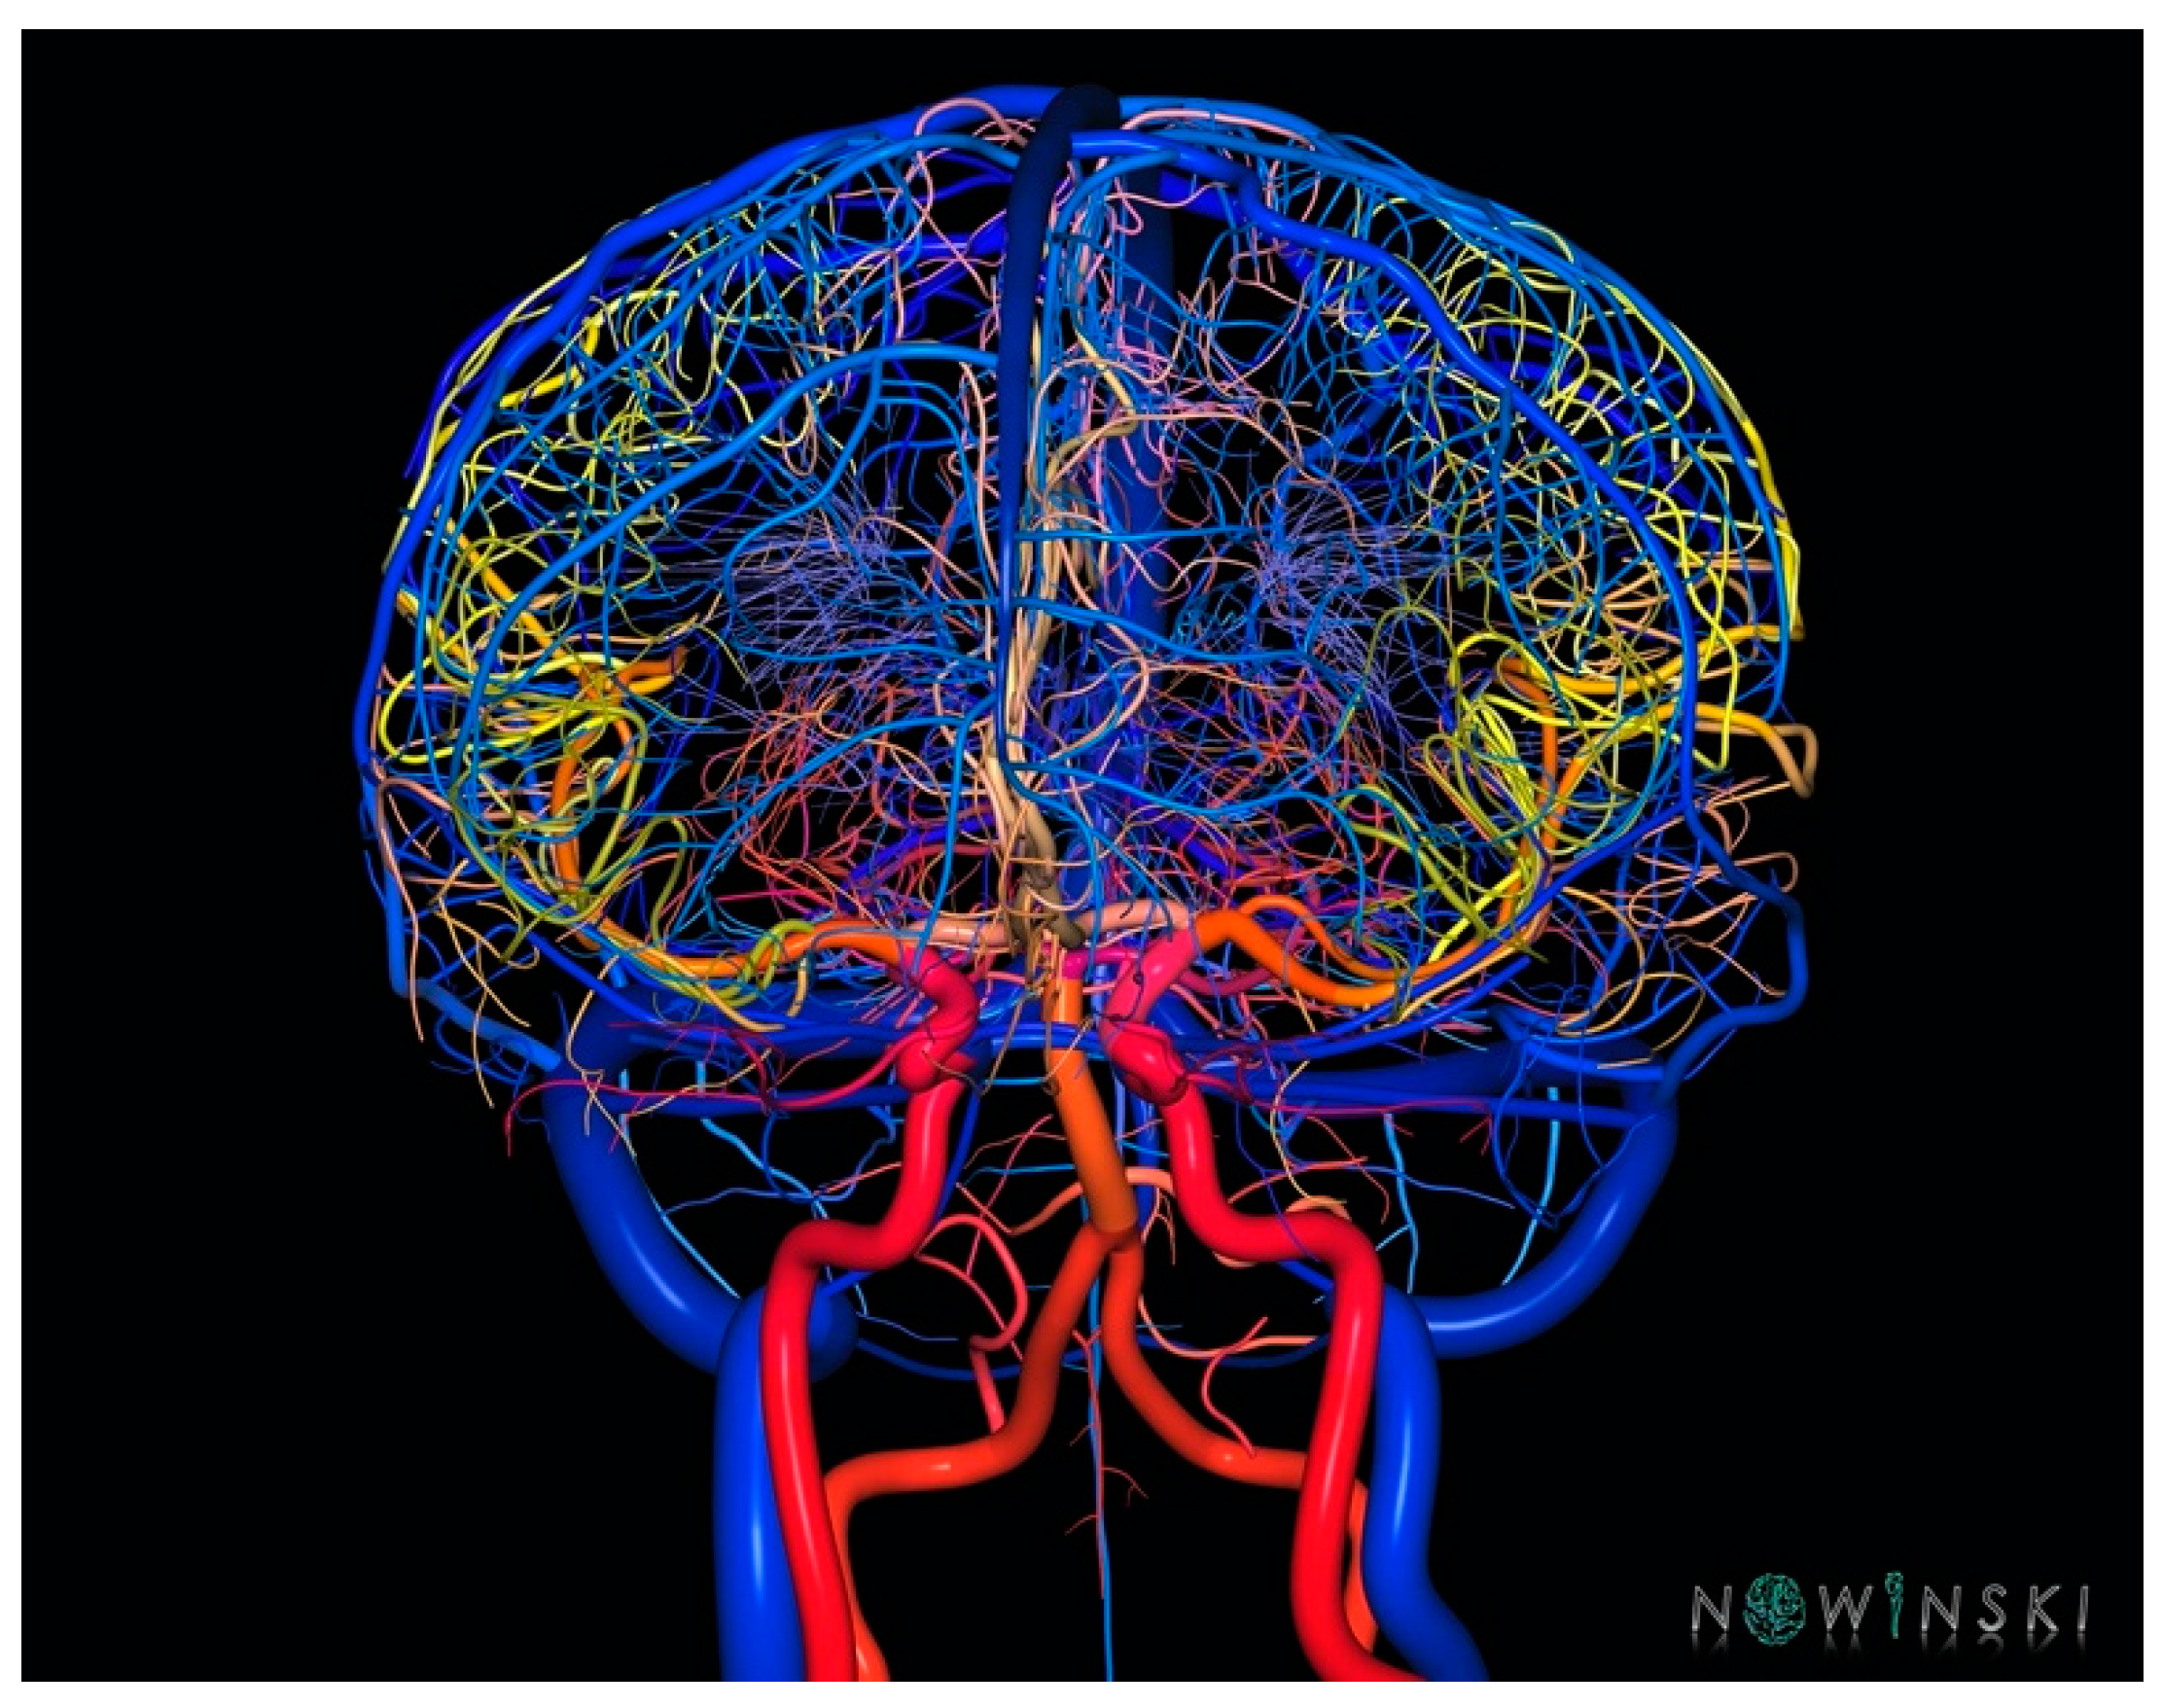

Human brain atlases have been widely used in clinical applications, particularly in stereotactic and functional neurosurgery. Initially, digital atlases such as The Electronic Clinical Brain Atlas were used offline in the operating room and later incorporated into surgical workstations such as the StealthStation to assist neurosurgeons in pre-, intra-, and post-operative support [52]. Brain atlases are useful for planning target and trajectory, identifying structures intersected by the trajectory, and specifying the structures already traversed by the electrode. They also measure distances to important structures, provide neuroanatomic and vascular context, and examine the precision of electrode placement. While current targeting techniques focus on the target point, atlas reporting cerebrovascular anatomy may assist in better placement of the entry point. Indeed, a small change in the entry point of a DBS electrode, occurring quite commonly especially in frameless DBS procedures, can lead to a major change in the trajectory. Nowinski et al. created an atlas of structure and vasculature with >900 vessels, with the smallest being 90 μm in diameter (Figure 13), it can be used to analyze the track–brain spatial relationship, allowing the DBS electrode to be placed more effectively, potentially reducing the invasiveness of the DBS procedure [80].

Figure 13.

A three-dimensional rendering of arterial and venous structures. Three-dimensional atlas of human vasculature can be used to analyze in DBS to analyze track–brain spatial relationship allowing the DBS electrode to be placed more effectively (from www.nowinbrain.org, accessed on 18 May 2023).